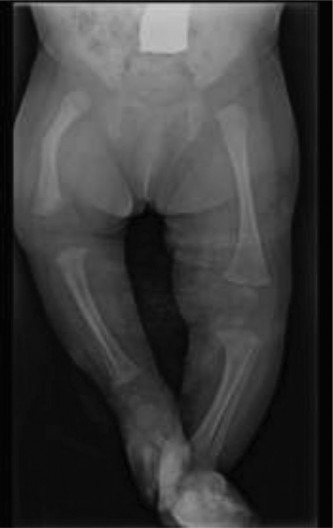

CASE 24 A healthy, 1-month-old baby is brought to see you because the right low…

CASE 40 The ER requests your consultation on a 3-year-old boy who presented wit…